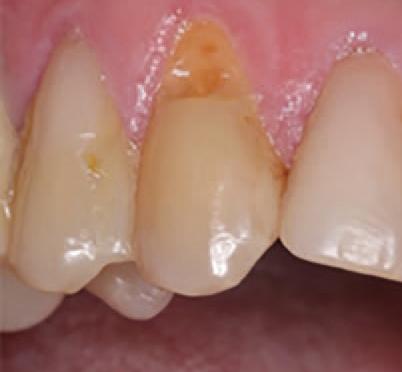

Case Study

Conservative Management of Class V Lesions: A Case Study Using Advanced Adhesive and High-Performance Flowable Composite

Patient Information

A 72-year-old male presented with a history of restoration loss and recurring sensitivity on tooth #6. The Patient reported that the previous restoration had dislodged, and he now experienced sensitivity localized to the cervical area. His medical history is non-contributory.

Diagnosis and Treatment Plan

Clinical examination confirmed the presence of a small lesion and sensitivity, likely due to exposed dentin.

Treatment Protocol: Caries Detection and Preparation

To improve isolation and soft tissue access, a retraction cord was placed before initiating the procedure (Fig. 2). The tooth was evaluated using a caries indicator dye (Kuraray Noritake Dental), helping to identify any remaining infected tissue beneath the dislodged composite (Fig. 3). Decay removal was completed with a diamond bur, and the enamel was bevelled using a starburst pattern to enhance aesthetic blending (Fig. 4). This preparation design was chosen for visual integration rather than bond strength enhancement.

Microabrasion

A PrepStart™ H2O Hydro Abrasion System (Danville Materials) was used to remove any residual plaque and biofilm, ensuring a clean bonding surface.

Etching and Bonding

Selective etching of the enamel was performed using a phosphoric acid etchant, followed by rinsing and air drying (Fig. 5). CLEARFIL™ Universal Bond Quick 2 was then applied according to the manufacturer’s protocol: a three second application, gentle airdrying, and light-curing for 20 seconds (Fig. 6).

Restoration Placement

CLEARFIL MAJESTY™ ES Flow Universal in shade UD (Universal Dark) was paced in 0.5mm increments, with each layer light-cured prior to the next (Figure 7).

Approximately 3-4 layers were used to fully restore the lesion to its final contour. (Figure 8). The spherical fillers and light scattering properties of the flowable composite allowed for seamless shade integration with the surrounding enamel.

Finishing and Polishing

A fine-grit diamond bur was used to shape and finish the restoration (Fig. 9). Final luster was achieved using a twostep polishing system from Meisinger USA (Fig. 10). The retraction cord was removed at the end of the procedure.

Rationale for Product Selection

In selecting restorative materials, I rely on products that are not only backed by solid research but also deliver consistently high performance in clinical situations. I used CLEARFIL™ Universal Bond Quick 2 and CLEARFIL MAJESTY™ ES Flow Universal for this case. CLEARFIL™ Universal Bond Quick 2 is extremely easy to use. It has a very thin viscosity that adapts to the tooth structure, and the application with a quick three second application, gentle air dry and light cure.

CLEARFIL MAJESTY™ ES Flow Universal has outstanding physical properties and aesthetic blending capabilities. The new spherical filler formulation allows it to scatter light and blend into surrounding tooth structure. Despite being a flowable, it has the strength and durability needed. I prefer working with sculptable materials that have a flowable but give me confidence in their long-term performance.

Patient Results

The patient reported immediate relief from sensitivity and was pleased with the natural appearance of the restoration. The conservative approach restored both form and function with minimal tooth reduction, while the selected materials ensured durability and long-term success.

Figure 1. Initial presentation of tooth #6 showing the Class V lesion with dislodged previous restoration and exposed dentin.

4. Preparation of the lesion completed with diamond bur and starburst beveling pattern to enhance aesthetic blending.

2. Placement of retraction cord to improve isolation and access to the cervical area prior to preparation.

Application of caries indicator dye to identify remaining infected tissue beneath the dislodged composite.